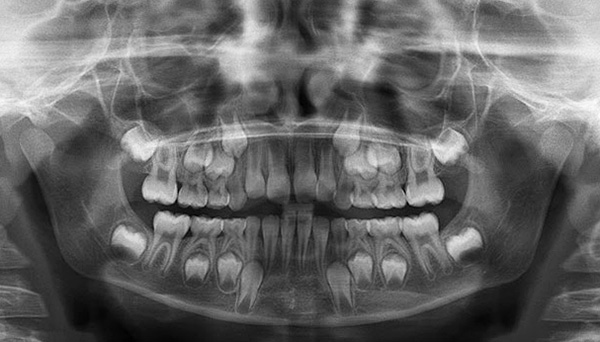

Nella radiografia in basso, i denti permanenti nell'osso, formati sotto il latte e pronti a spingerli, sono chiaramente visibili:

In ogni caso, solo il dentista può capire il motivo del ritardo nella sostituzione dei denti temporanei dopo l'esame: verrà eseguita una radiografia. Dopo aver valutato l'immagine, l'ortodontista discute le opzioni di trattamento.